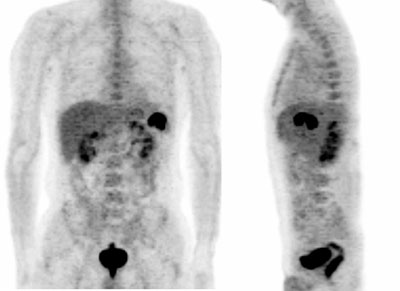

Fig. 3. - Imágenes coronal de tomografía por emisión de positrones de cuerpo completo. Varón de 44 años en estudio por sospecha de linfoma y antecedentes de parotiditis. En el estudio se aprecian diversos focos patológicos en localización iliaca, inguinal, mediastínica y cervical; así como un aumento del metabolismo en ambas parótidas (principalmente en tercio inferior de la izquierda).